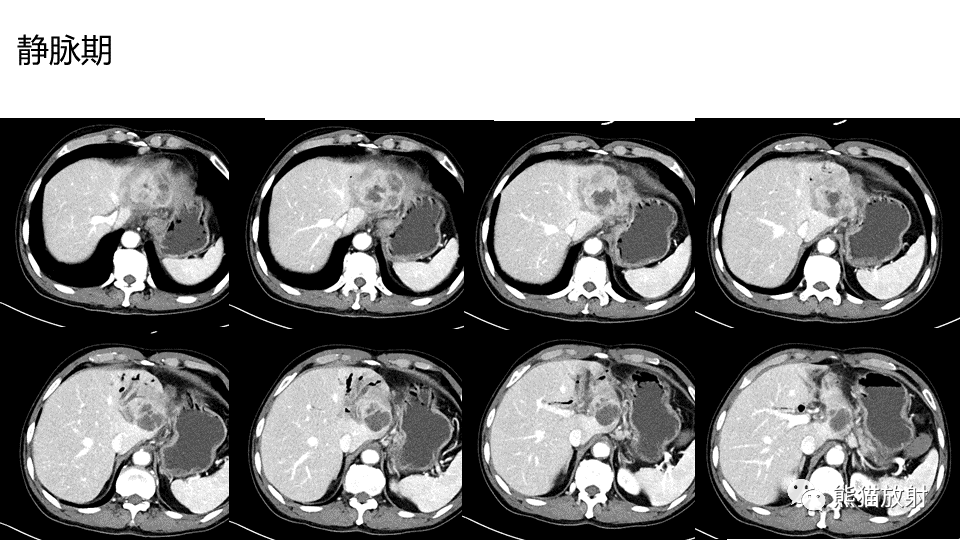

【PPT】肝内胆管细胞癌 VS 肝脓肿